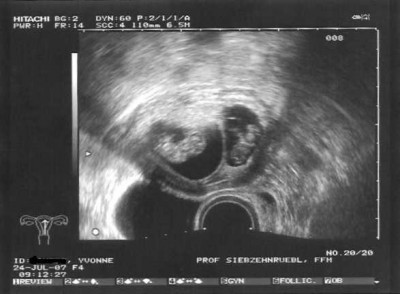

Der Prof. war mit mir zufrieden der US war super die Babys sind jetzt schon 3 cm groß. Das kleinere ist nur 1mm kleiner und das mit dem zuwenigen Fruchtwasser hat sich auch gegeben. Jetzt ist alles super in Ordnung. Die Herzlein haben geschlagen und die kleinen haben sich auch schon bewegt. Wie süß.....

US 16.07.07 2 Herzlein schlagen Zwillinge